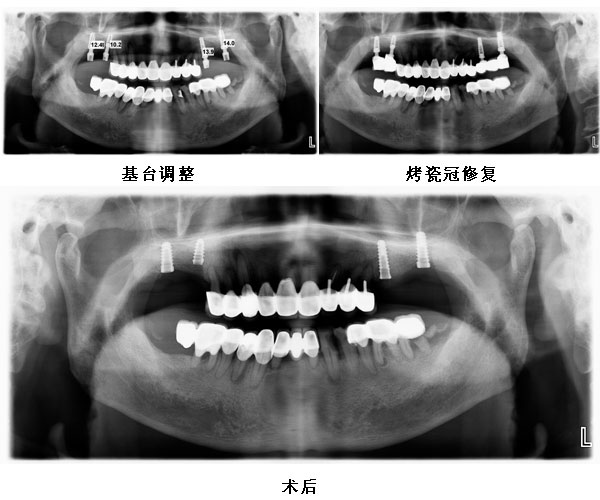

患者左右上颌四颗后牙种植修复